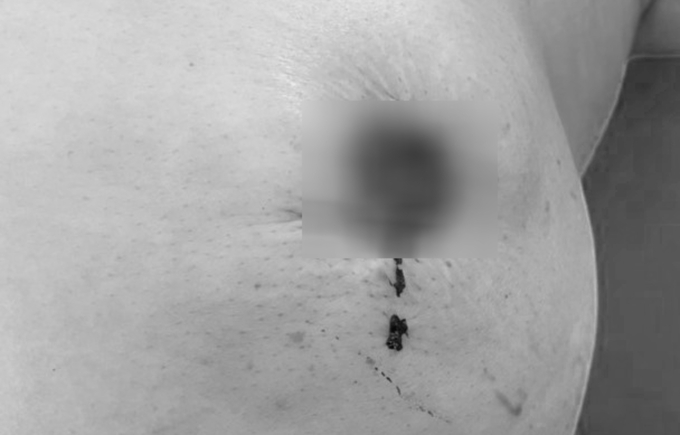

5. Mất núm vú do đắp thuốc nam chữa ung thư

Người phụ nữ 49 tuổi, ở Tây Ninh, đắp thuốc nam tự chữa ung thư vú khiến bầu ngực lở loét, mất núm, chảy máy liên tục

Nguồn: https://vnexpress.net/mat-num-vu-do-dap-thuoc-nam-chua-ung-thu-4253267.html

Bệnh nhân bị "rụng" núm vú do dùng thuốc nam chữa ung thư, nay phải phẫu thuật đoạn nhũ. Ảnh: Bệnh viện cung cấp